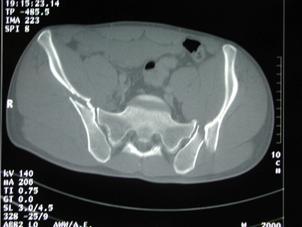

Luxatie de sold stang Luxatie de sold stang

Fractura

de cap femural Fractura de cap femural

Aspect

CT